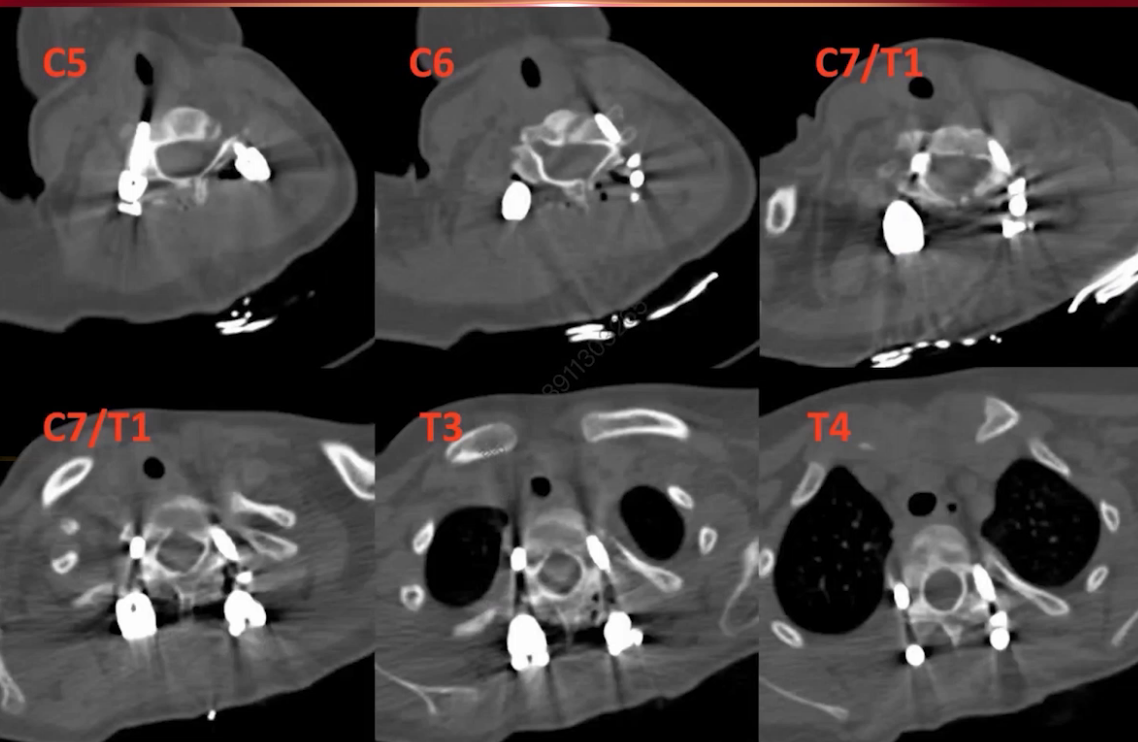

CT显示C5-C7椎体分界不清,伴对侧骨桥形成。三维重建更清晰展示局部畸形结构。